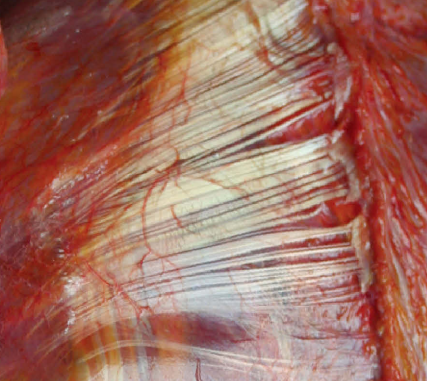

在遠端肌筋膜放松組,患者躺治療床上,雙腳懸在床外,以進行小腿筋膜放松。治療師站在患者旁邊,握緊雙手,將雙拇指完全伸展放在腘窩處。

治療師保持雙肘伸展以更好施力,并用雙拇指從腘窩處向腳跟方向推移。要求患者將腳置于背屈狀態(tài),然后在施加手法時慢慢自主回到背屈位置。這個操作重復(fù)5次(圖3)。

(圖3 小腿筋膜的放松)